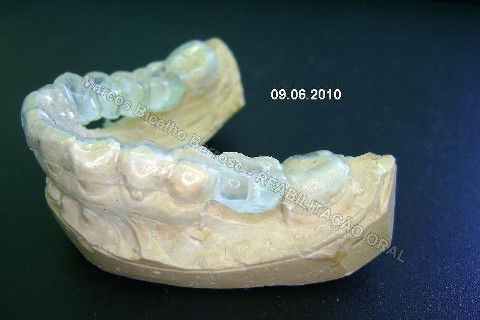

Paciente sexo feminino, 40 anos, queixava-se da situação da PPR superior, sem estabilidade, fraturas constantes nos dentes instalados. Sua vontade era resolver somente o problema da arcada superior, por questões financeiras. Logo no exame clínico inicial verifiquei a necessidade da reabiltiação inferior, pois este caso consistia em desarmonia oclusal severa, principalmente pela extrusão dos elementos 13,14 e 15 devido ausência de várias unidades inferiores. A proposta aceita pela paciente foi a instalação de 5 implantes na mandíbula + 5 implantes na maxila + tratamento endodôntico, osteoplastia e gengivoplastia nos dentes extruídos, incluindo núcleos metálicos e coroas em metalocerâmica (13,14,15). As coroas sobre implantes serão incialmente provisórias em resina fotopolimerizável e posteriormente metalocerâmica, de acordo com as possibilidades da paciente. Os procedimentos nos elementos extruídos serão apresentados em momento oportuno.